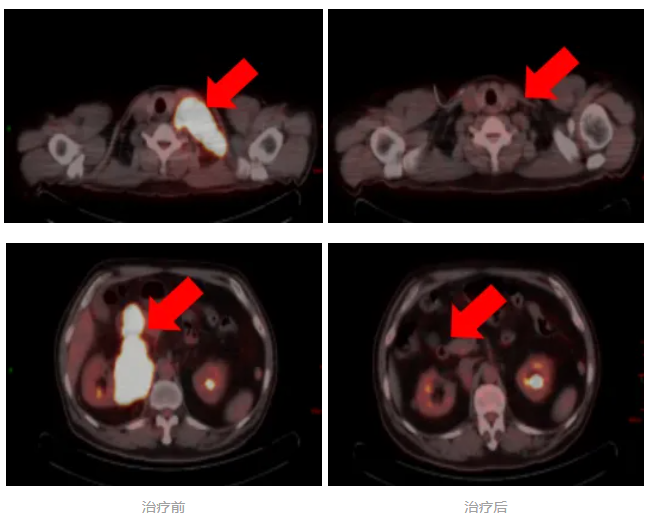

日前,一例高危、双表达型弥漫大B细胞淋巴瘤患者,在我院淋巴瘤及头颈肿瘤内科接受个体化精准治疗后,病情得到有效控制,疗效评价达到完全缓解(CR)。

患者因左颈部肿物就诊我院,经穿刺活检初步诊断为弥漫大B细胞淋巴瘤。为全面评估病情,医疗团队进一步完善检查,最终明确为高危型弥漫大B细胞淋巴瘤,已广泛累及淋巴结、肠管及胰腺,治疗难度较大。

经4周期治疗后,评估为部分缓解(PR)。为改善患者预后,MDT团队再次讨论并与患者沟通后,在后续治疗中加用组蛋白去乙酰化酶抑制剂。完成系统治疗后复查显示,患者最终达到完全缓解。